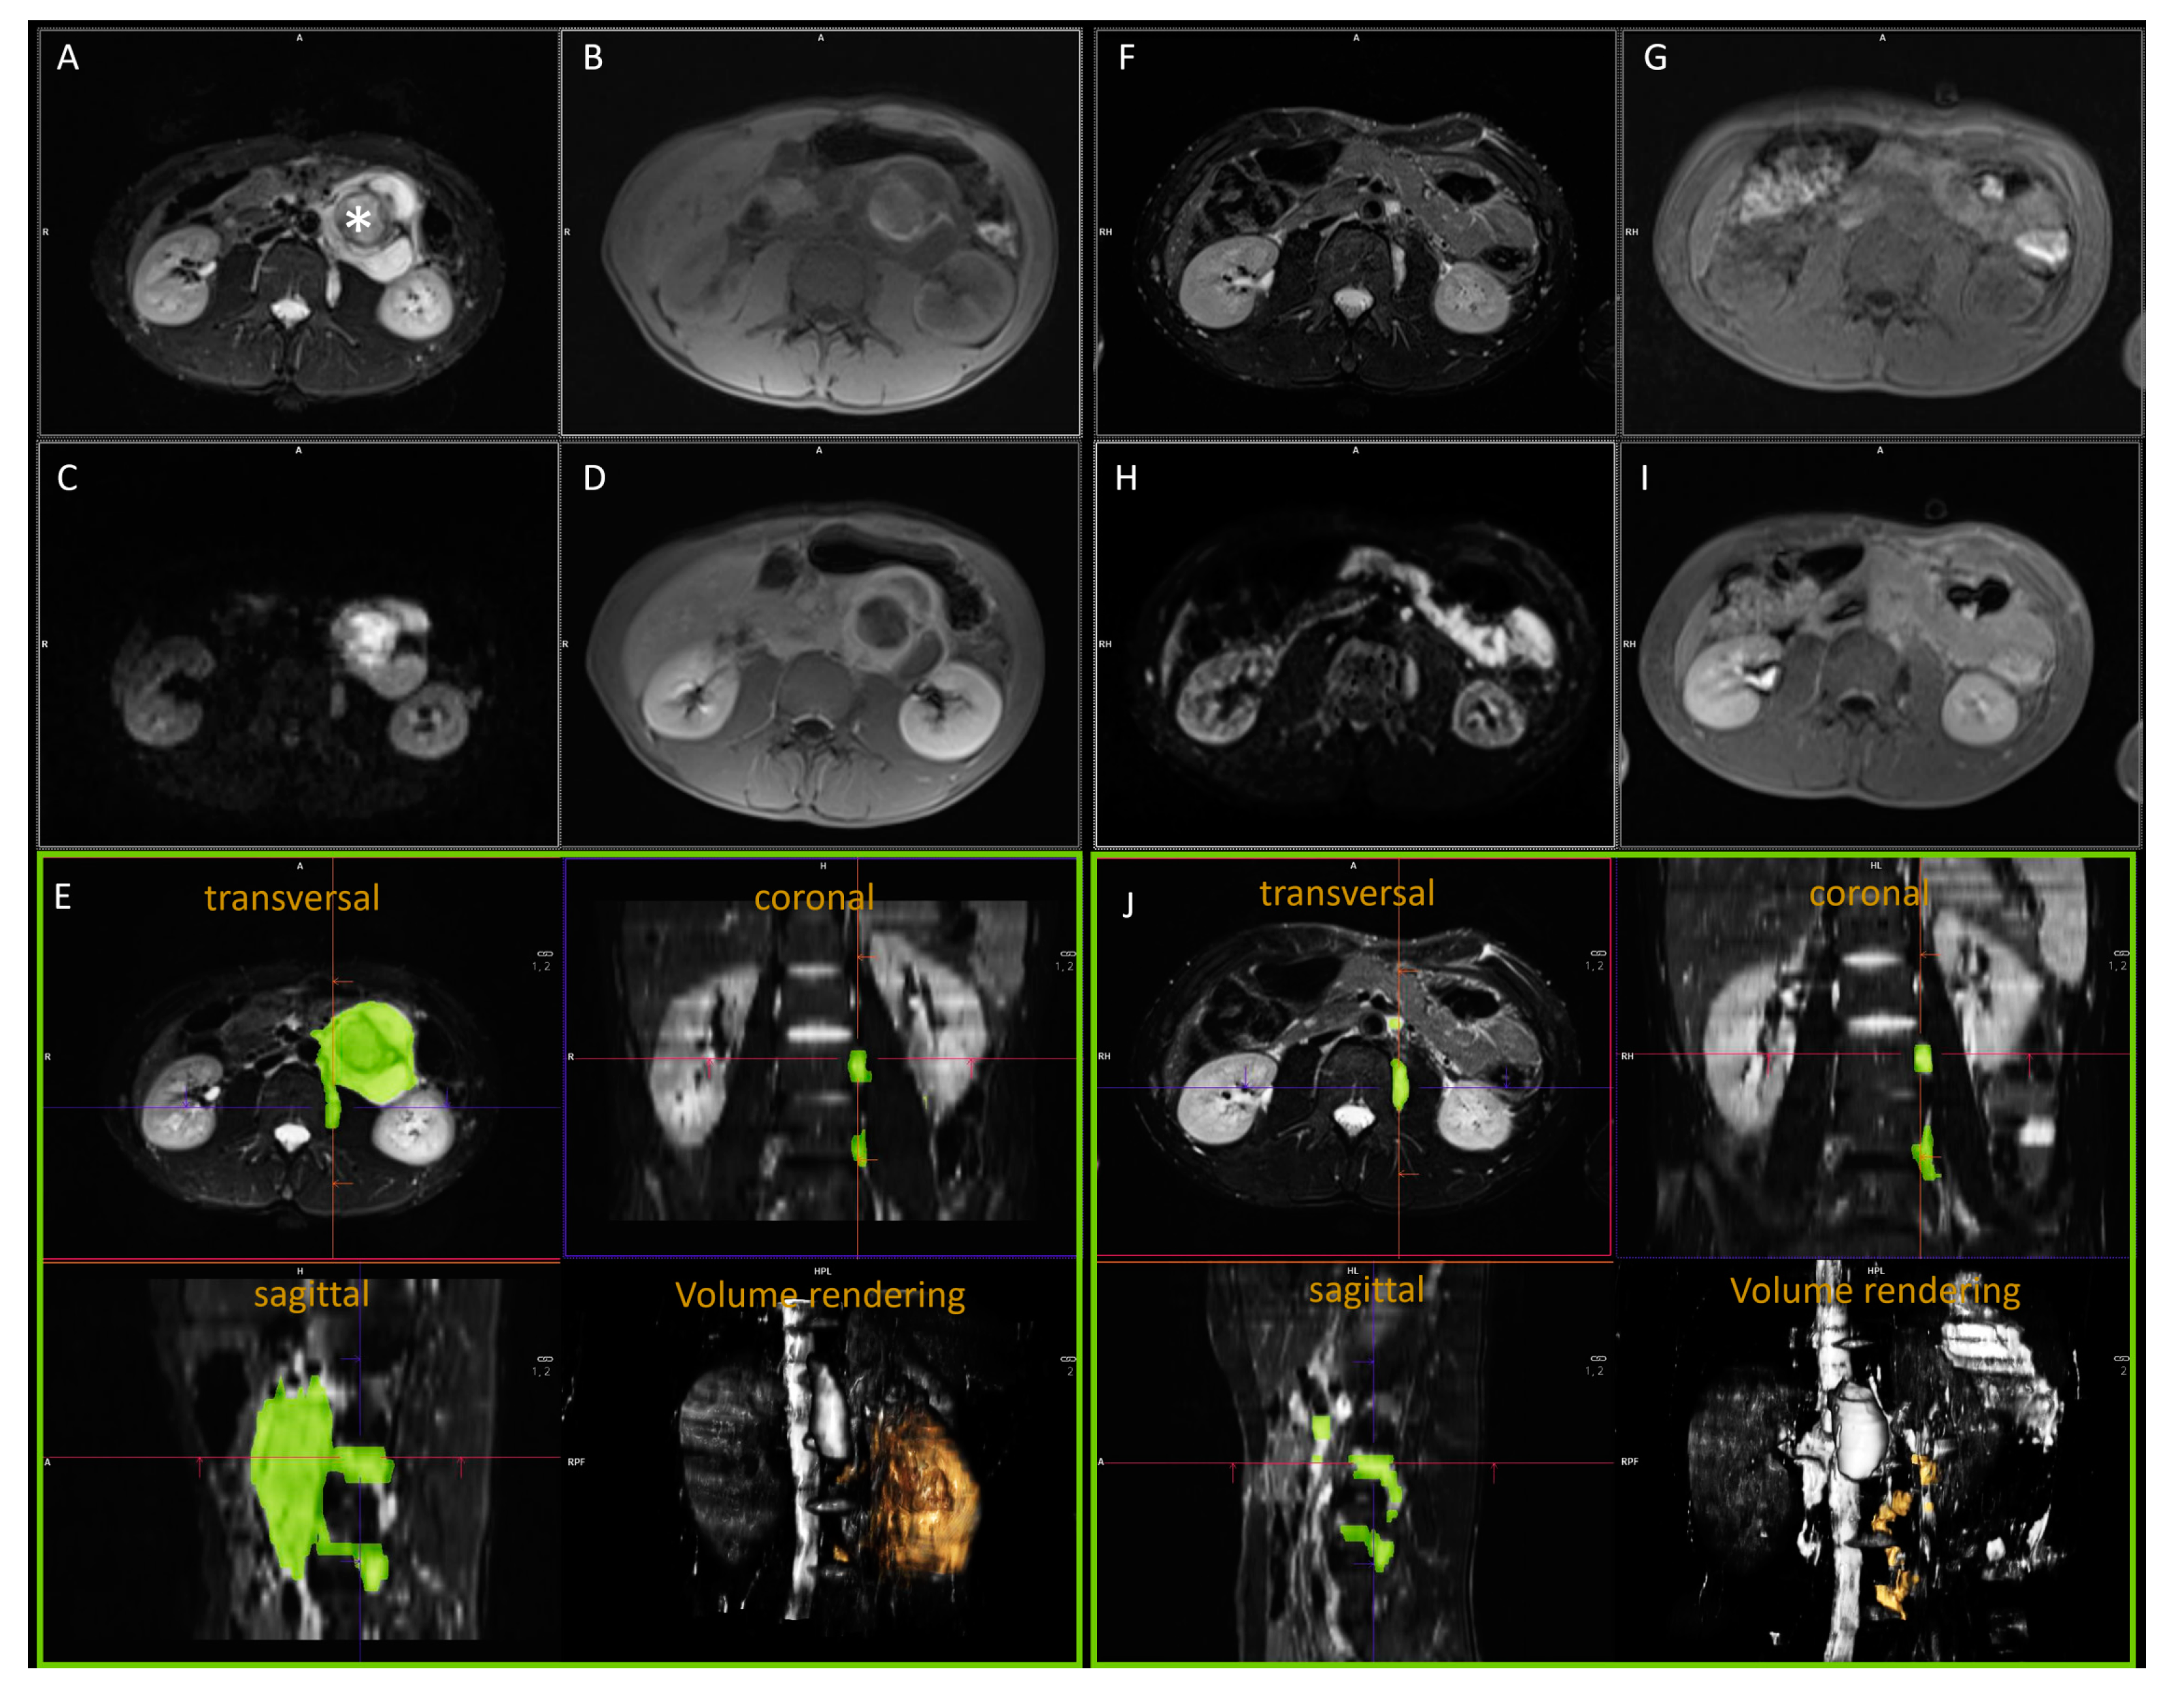

- Gassenmaier, S.; Tsiflikas, I.; Fuchs, J.; Grimm, R.; Urla, C.; Esser, M.; Maennlin, S.; Ebinger, M.; Warmann, S.W.; Schafer, J.F. Feasibility and possible value of quantitative semi-automated diffusion weighted imaging volumetry of neuroblastic tumors. Cancer Imaging 2020, 20, 89. [Google Scholar] [CrossRef]

- Peschmann, A.L.; Beer, M.; Ammann, B.; Dreyhaupt, J.; Kneer, K.; Beer, A.J.; Beltinger, C.; Steinbach, D.; Cario, H.; Neubauer, H. Quantitative DWI predicts event-free survival in children with neuroblastic tumours: Preliminary findings from a retrospective cohort study. Eur. Radiol. Exp. 2019, 3, 6. [Google Scholar] [CrossRef] [PubMed]

- Neubauer, H.; Li, M.; Muller, V.R.; Pabst, T.; Beer, M. Diagnostic Value of Diffusion-Weighted MRI for Tumor Characterization, Differentiation and Monitoring in Pediatric Patients with Neuroblastic Tumors. Rofo 2017, 189, 640–650. [Google Scholar] [CrossRef]